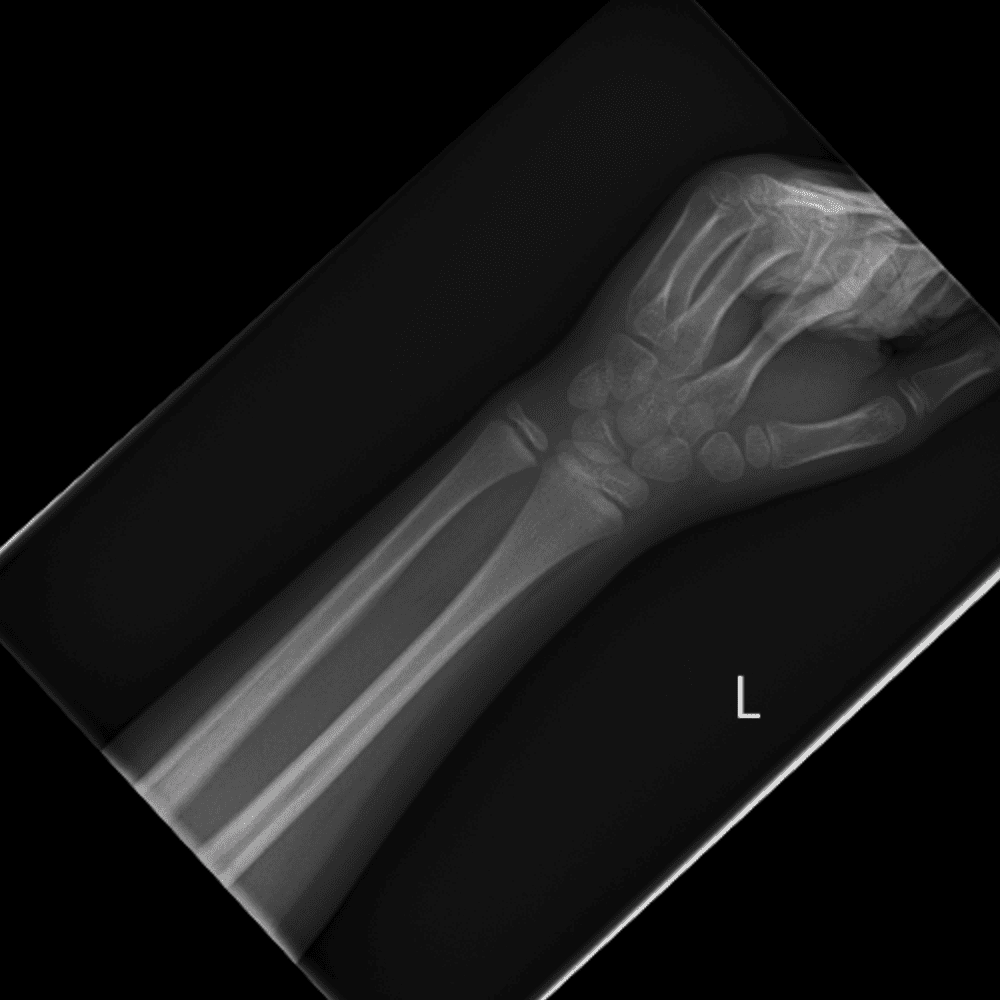

Simulates call by including subtle or difficult cases and some normals.

30 cases